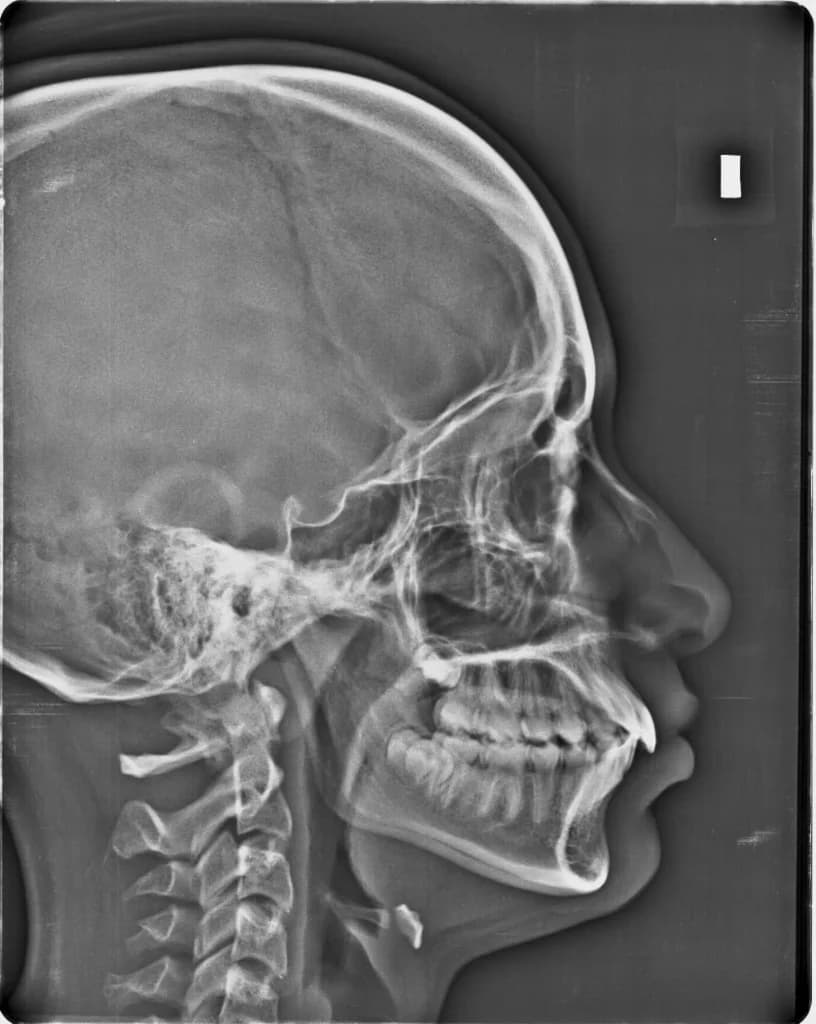

Panoramic X-Rays: The Complete Picture

Panoramic x-rays capture your entire mouth—all teeth, upper and lower jaws, sinuses, and TMJ joints—in a single, wide-angle image. It's like a dental "panorama" that shows relationships between structures.

We use panoramic x-rays for comprehensive exams, orthodontic planning, wisdom teeth evaluation, and screening for jaw abnormalities. The process takes about 10 seconds—you simply stand still while the machine rotates around your head.